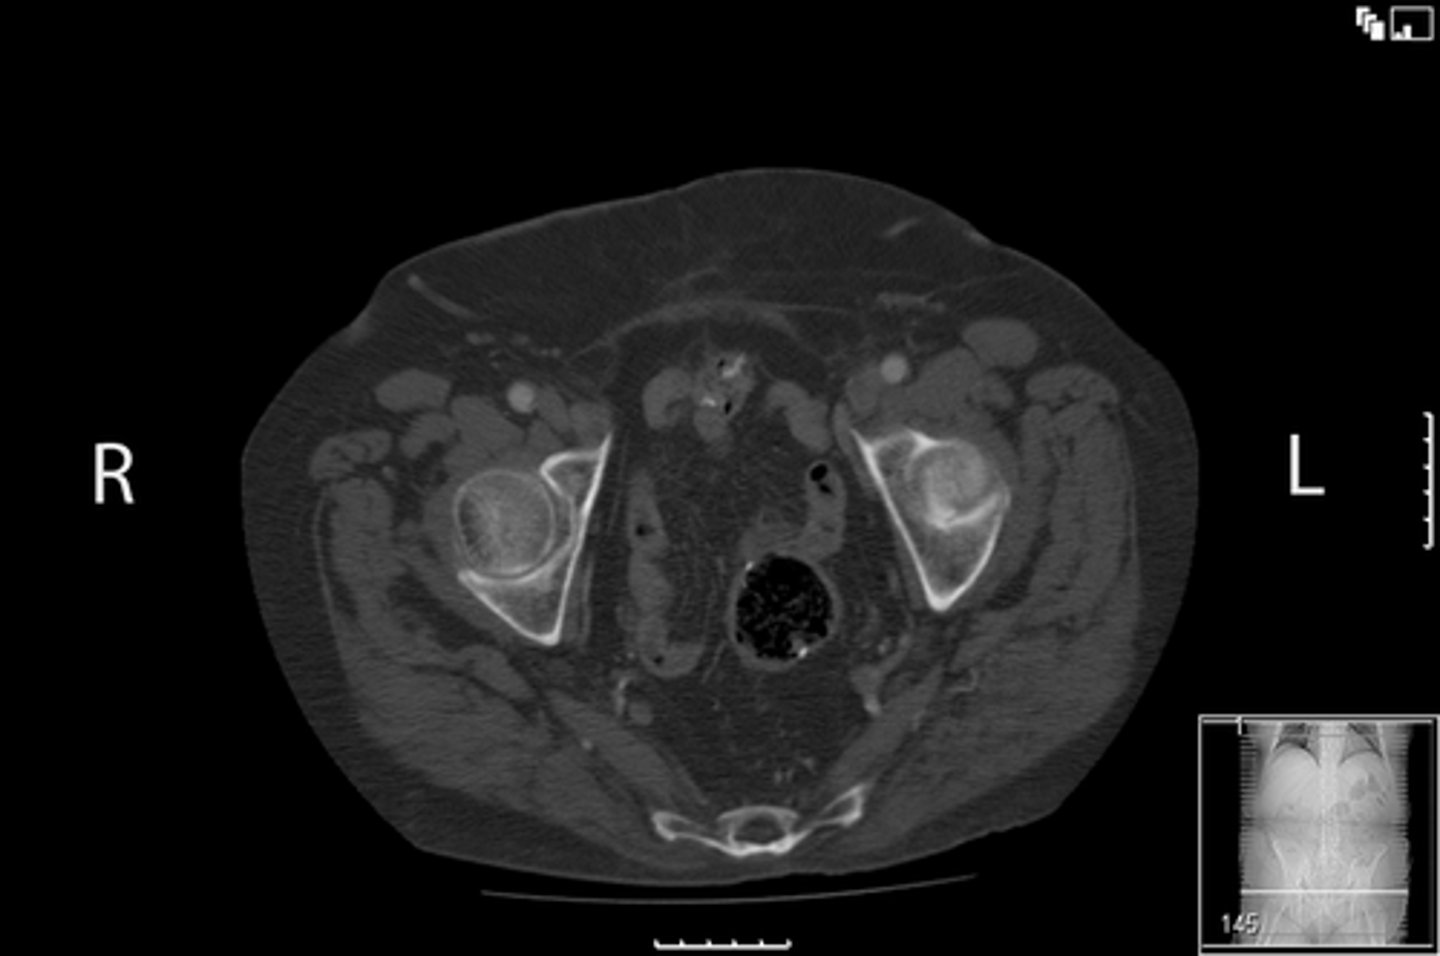

Axial bony pelvis CT

What is the image?

<p>What is the image?</p>

32

New cards

L ilium

What is indicated in the image?

<p>What is indicated in the image?</p>

33

L sacroiliac joint

34

R ilium

35

R sacroiliac joint

36

Sacrum

38

L acetabulum

39

L femoral head

40

L piriformis muscle

41

R femoral head

42

R piriformis muscle

43

R acetabulum (posterior part)

44